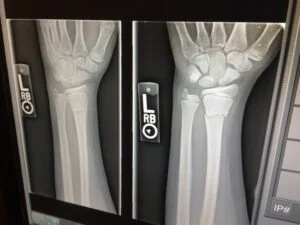

Fractures can occur on the inside or outside of the leg. Fractures can cause pain, swelling, and bone deformities. Rapid “reduction” is essential (setting the bones together to heal) and X-rays can be helpful. Open surgery may be necessary in extreme cases to reduce fractures. Pins, screws and plates are often used to maintain the reduction.